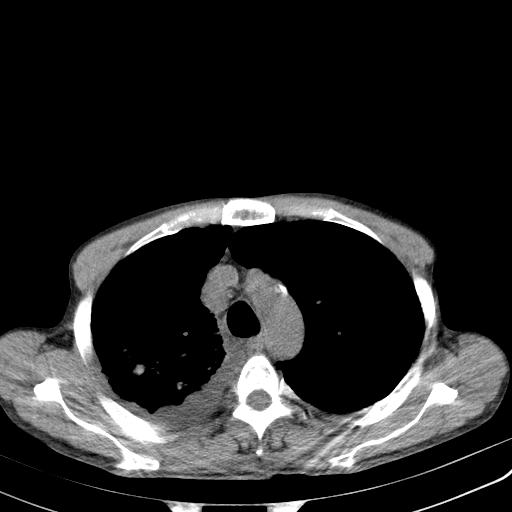

男性 75  咳嗽 一周前发热最高达39

右肺继发型tb并右侧tb性胸腔炎,右侧胸腔大量积液并右下肺膨胀不全,慢支肺气肿、多发肺大泡。建议抽胸水实验室检查并复查排除恶性在占位。

右上肺继发型肺结核,右胸腔中等量积液。

1)右肺继发型肺结核。2)左肺胸膜下多发性肺大泡。3)右侧胸腔积液。